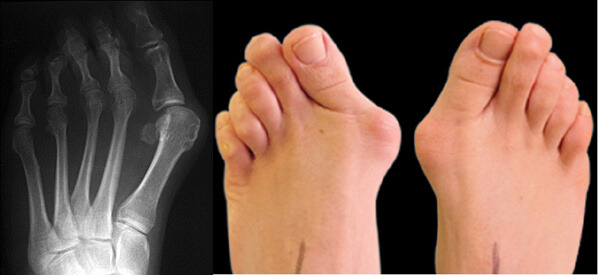

무지외반증

하이힐을 신으면 가장 대표적으로 나타나는 부작용인 무지외반증. 엄지발가락이 발등이나 새끼발가락 쪽으로 기울어져 모양을 변형해 통증을 유발하는 질환이다. 하이힐이나 킬힐 같은 높은 구두를 장시간 신을 경우 발 앞쪽이 지속적으로 압력을 받아 발생하게 된다. 그래서 남성보다 여성에게 발생하기 쉽고 그 확률은 90%에 달한다. 또한, 본격적으로 구두를 많이 신는 20대 전반부터 흔하게 나타나기 시작한다. 앞 코가 좁거나 사이즈가 작은 신발을 신을 경우에도 발생하는 경우가 있으니 되도록 편한 구두를 신는 것이 좋고 변형이 심해지지 않도록 보존 치료를 추천한다.